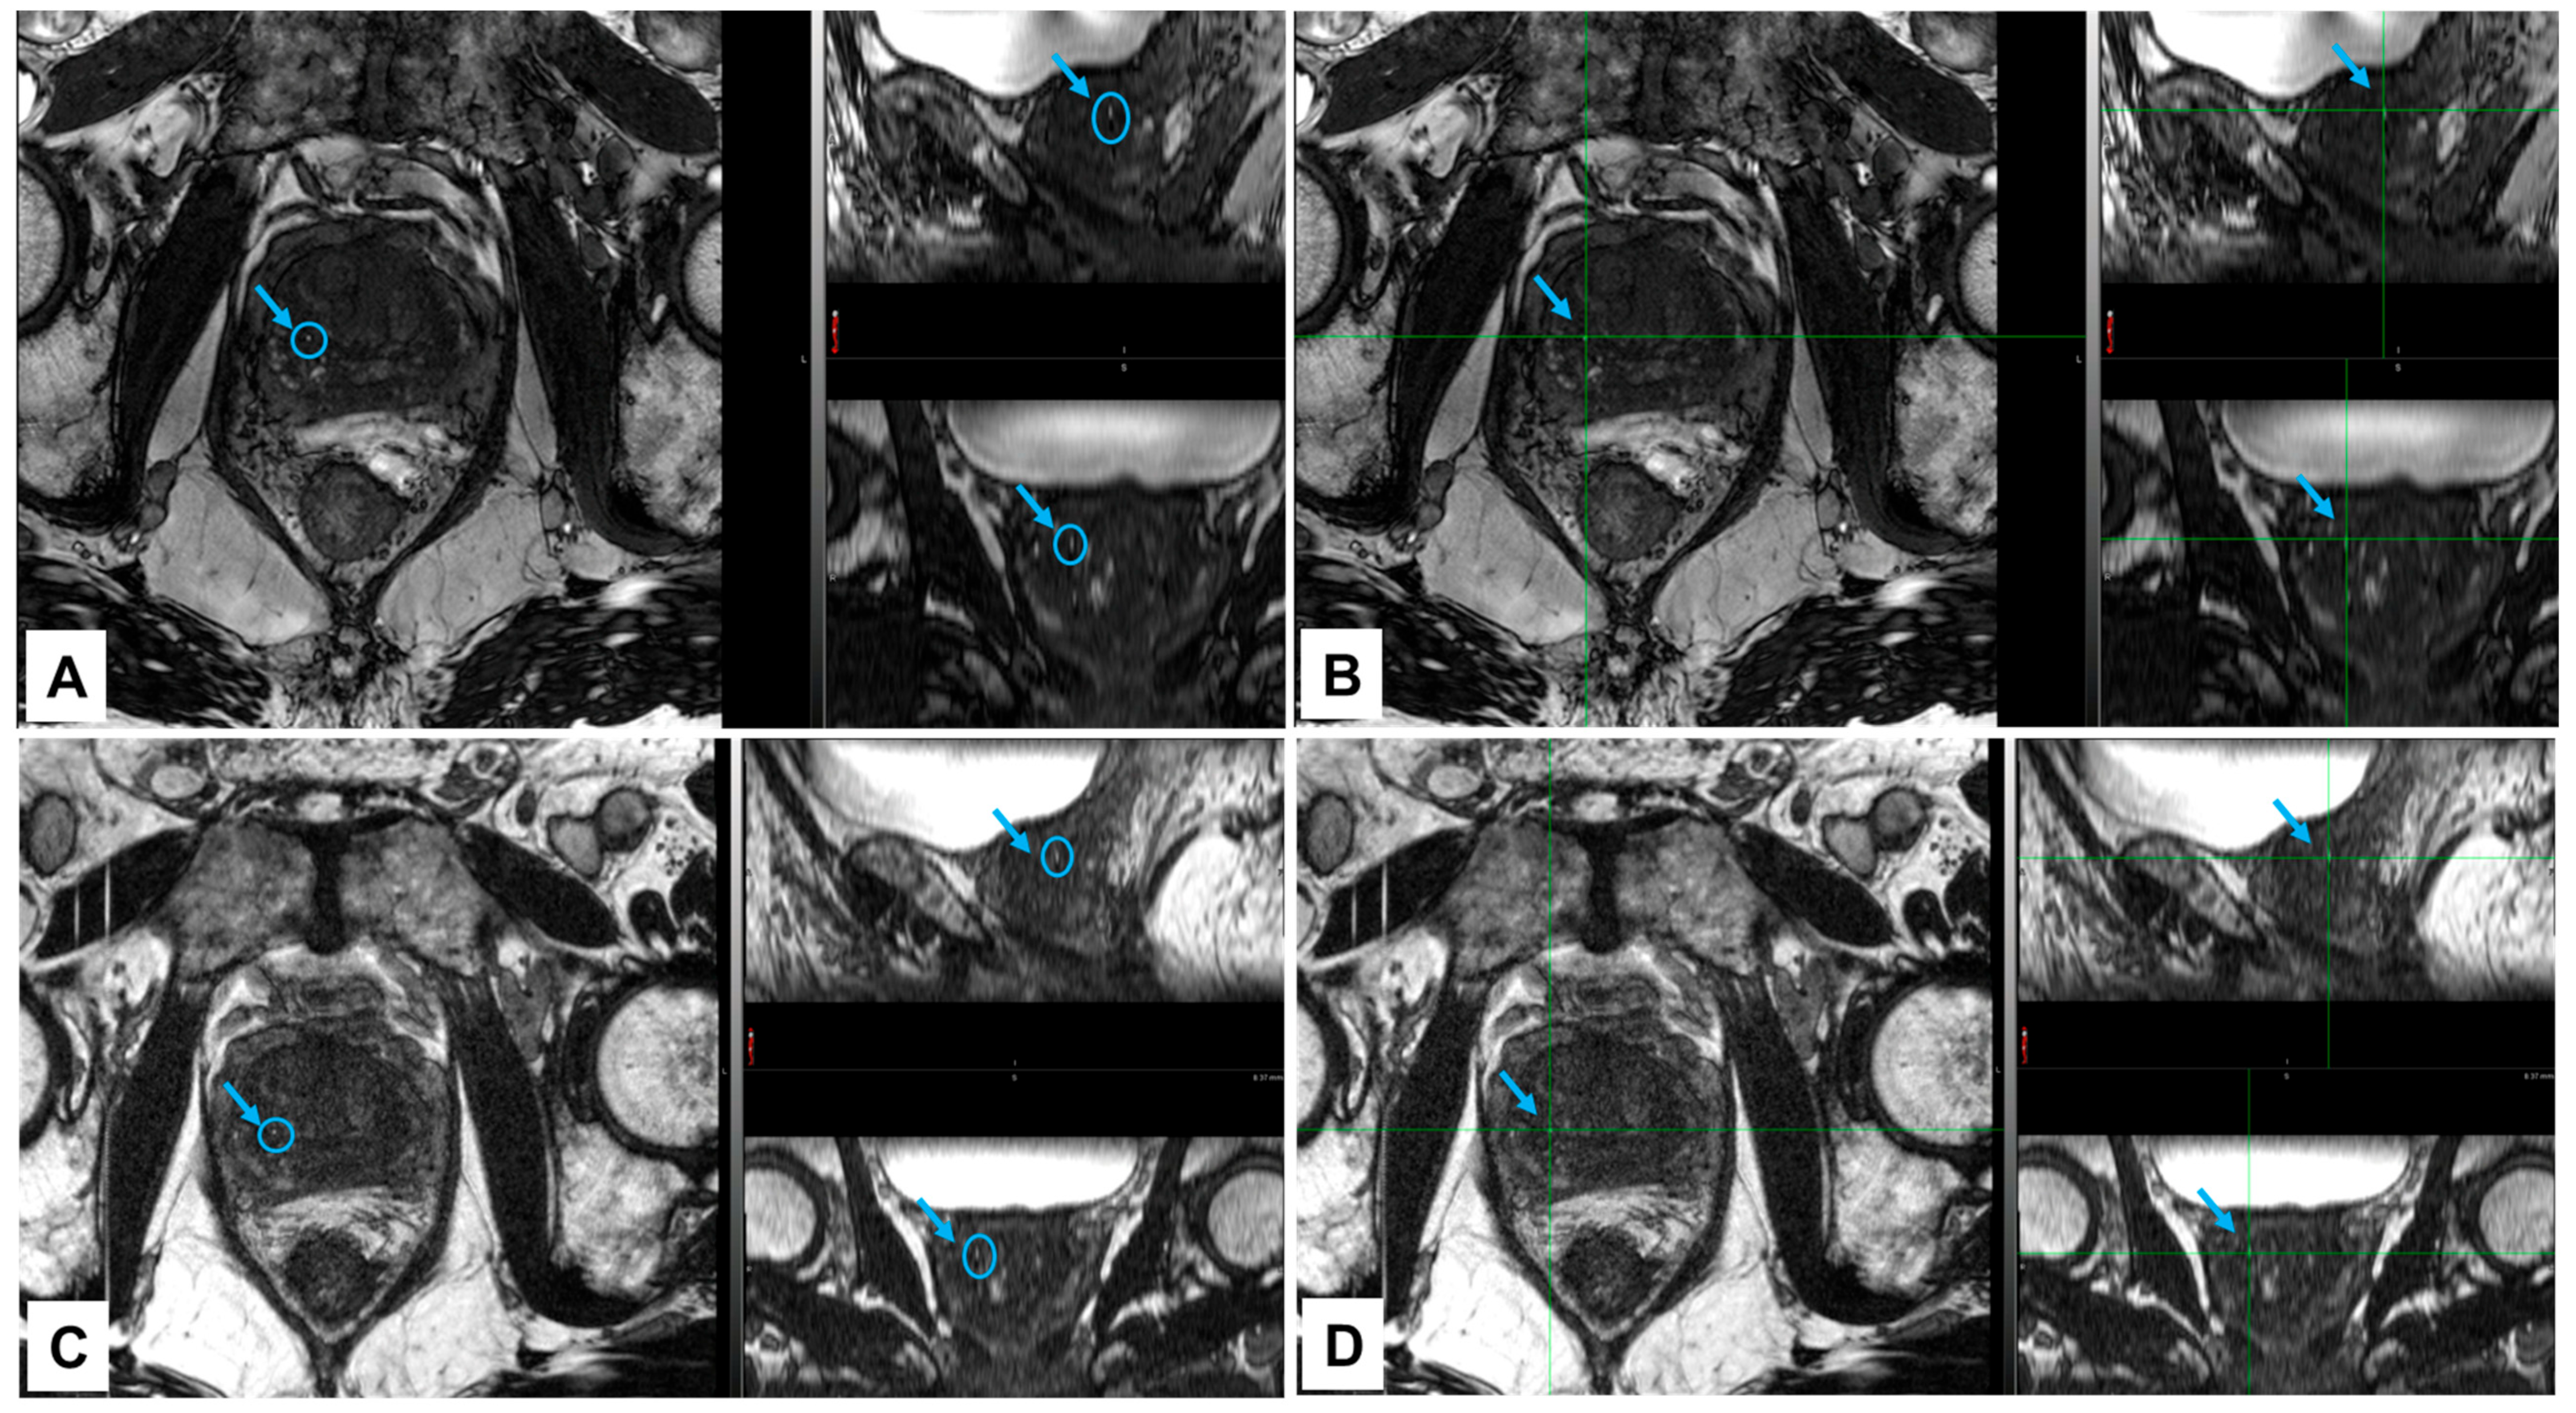

2.8. MRI/CT Image Fusion

3.4. Visibility of NOVA Markers in a Clinical Case